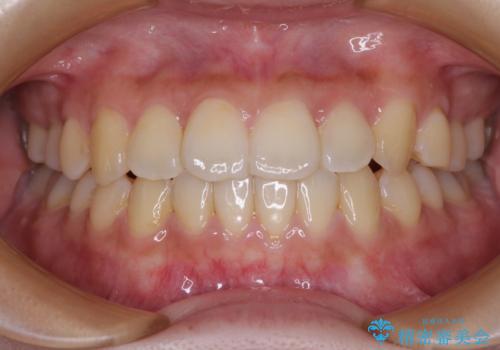

- 出っ歯と口の閉じにくさ、デコボコを気にして来院された患者様です。

口元の突出感を改善するため、上下左右第一小臼歯4本の抜歯を行い、ワイヤー装置による矯正治療を行うこととしました。

上下前歯の距離が大きかったため、上下の歯が接触するまでに時間がかかりました。

それでも目安である2年半で終えることができ、患者様には大変満足していただけました。